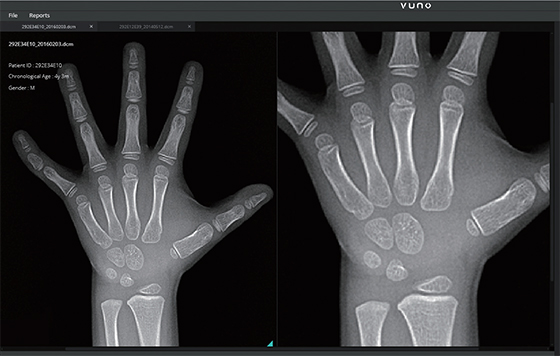

뷰노의 딥러닝 검증 시스템. (사진=뷰노) |

서울 강남구 논현동에 위치한 뷰노(VUNO)는 딥러닝/기계학습 기술을 이용한 의료용 소프트웨어 개발회사다. 주요 고객은 병원, 의료기관. 고급 두뇌들이 기업을 이끈다는 점이 특색 있다. 14명의 구성원 가운데 7명이 박사학위를 가지고 있었다.

회사 창설 과정에 대해, 김현준 이사는 “삼성종합기술원에서 딥러닝을 이용한 음성인식 엔진을 개발하던 팀 동료 3명이 공동 창업했다”고 설명했다. 이러한 기술은 쉽게 이해하기 힘든 면이 있다. 좀 더 쉽게 설명해달라고 요청하자, 김 이사는 “의료 현장의 방대한 데이터를 기반으로 병의 증상을 자동으로 예측하는 기술”이라며 “의료진의 효율적인 의사결정을 위한 정보를 제공하는 것이 목적”이라고 설명했다. 의료진단을 컴퓨터에 물어보는 시대가 이미 도래한 것이다. 뷰노에 따르면 의료영상, 생체신호, 의무기록 등을 통해 ▲병의 위치를 탐구하고 ▲이상 신호를 조기에 예측하며 ▲이상 여부를 사전, 사후에 판별해 궁극적으로 질병 위험도를 예측하는 기술을 발전시키고 있었다. 이러한 기술 개발을 위해서는 병원과 협력해야 한다. 뷰노는 분당서울대병원, 서울아산병원, 삼성서울병원 등과 질병별 보조 소프트웨어 개발을 추진하고 있다.

뷰노의 분석 솔루션. (사진=뷰노) |

뷰노의 비전은 무엇일까. 김 이사는 “구글, 페이스북 등 글로벌 IT기업이 딥러닝 기술의 대부분을 선도하고 있다”며 “비록 글로벌 대기업이 다양한 오픈소스를 제공하고 있지만, 최신 기술의 경우 어렵다. 이러한 기술 종속을 탈피하고자 자체 엔진을 개발해 최신 기술을 앞서서 확보하는 것이 목표다”라고 설명했다. 실제로 뷰노는 자체 엔진을 개발하고 있었다. 정보를 통합 분석하는 엔진은 인공지능 산업의 기본이다. 뷰노가 개발한 엔진은 어떤 것인가. 김 이사는 “다양한 문제를 학습하는 딥러닝 기술을 계속 향상시키고 있다”며 “기술에서 학습시간 단축이 중요한데, 같은 시간 내에 더 많은 데이터를 학습할 수 있기 때문에 성능 향상에 중요하다”고 설명했다.

2016년 3월 바둑에서 기계가 인간의 능력을 앞선다는 사실이 입증됐지만, 인간의 생명까지 기계에 의존할 수 있을지는 의문이 들었다. 목숨이 걸린 일이기 때문이다. 이러한 의문에 대해 뷰노 측은 구체적인 임상 데이터로 설명했다. 우선 미만성 간질환의 경우, 6개 질환 패턴을 분류하는 성능을 과거 최고 성능 91.1%에서 96.7%로 5.6% 향상시켰다. 서울아산병원과 협력해 내린 진단에는 1200명의 환자 데이터가 이용됐다. 빈맥성부정맥(심장마비) 조기 예측도 성과가 있었다. 심장마비를 예측하는 기술로, 과거 최고 성능 76.6%에서 89.6%로 13% 향상시켰다.